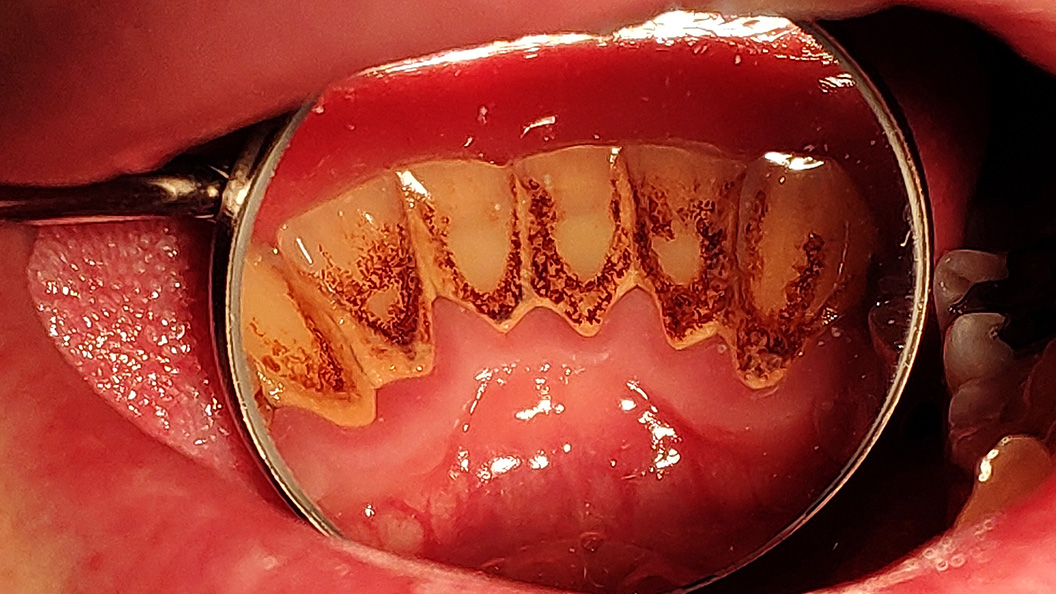

До и после лечения

В нашу клинику обратился пациент с жалобами на наличие зубных камней и сильную кровоточивость дёсен во время чистки зубов.

На момент осмотра были обнаружены над- и поддесневые зубные отложения, пигментированный зубной налёт на всех зубах, маргинальная десна отёчна и гиперемирована, при зондировании кровоточит. При этом патологическая подвижность зубов и пародонтальные карманы отсутствуют. Наш специалист Черных Антон Алексеевич рекомендовал проведение профессиональной гигиены полости рта.